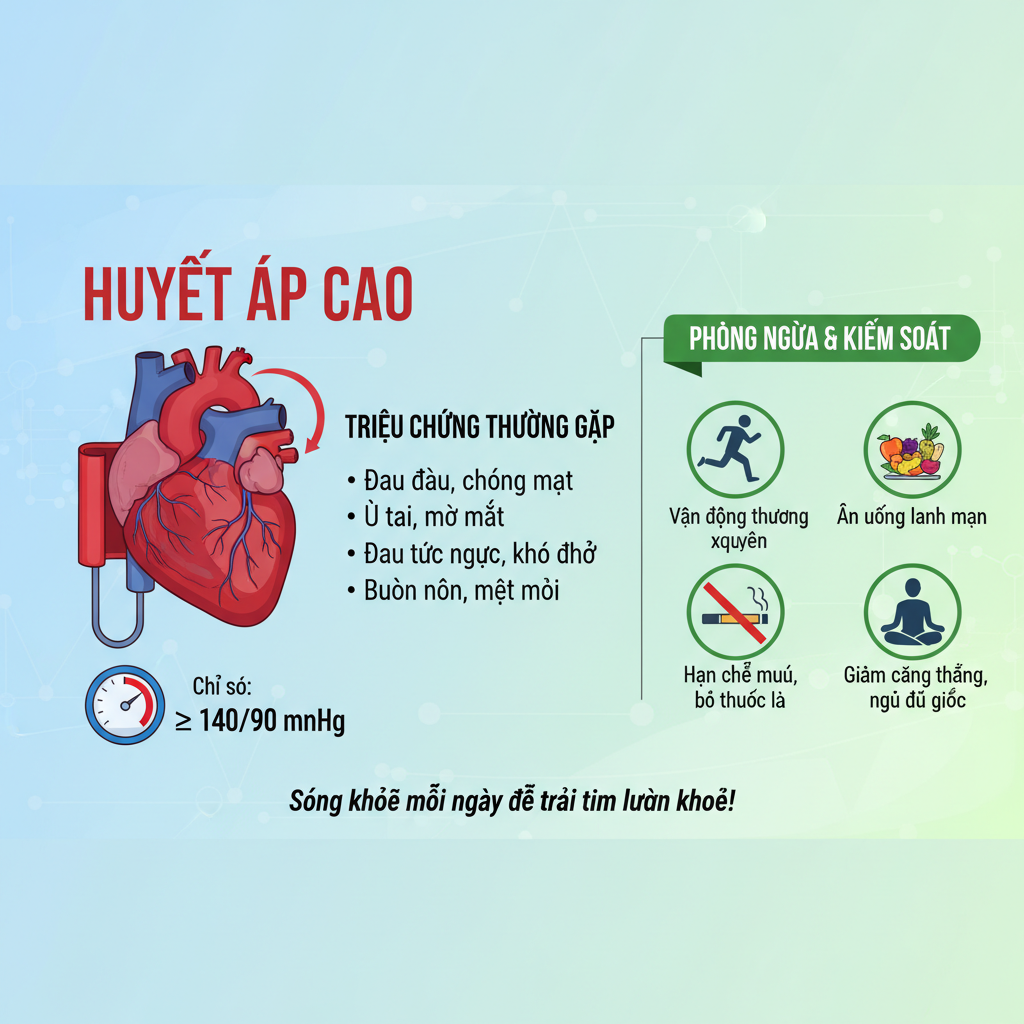

Cao huyết áp là một bệnh lý phổ biến, nhưng với những hiểu biết đúng đắn về chế độ ăn uống, chúng ta có thể kiểm soát được bệnh. Bài viết này sẽ cung cấp thông tin cần thiết để bạn hiểu rõ hơn về...

Cao huyết áp là một bệnh lý phổ biến, nhưng với những hiểu biết đúng đắn về chế độ ăn uống, chúng ta có thể kiểm soát được bệnh. Bài viết này sẽ cung cấp thông tin cần thiết để bạn hiểu rõ hơn về...